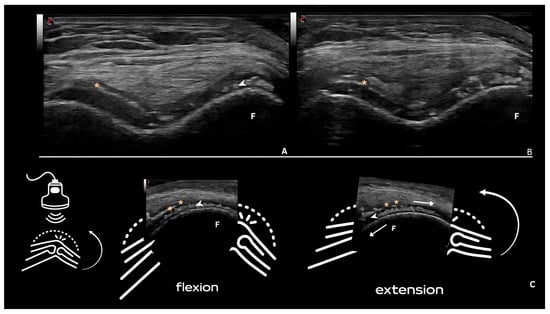

| Hyaline cartilage | Shape: Deposits of variable shape. Echogenicity: Hyperechoic, without posterior shadowing. Localization: Localized within the hyaline cartilage. Dynamic scanning: The deposits remain fixed and move together with the hyaline cartilage. Examples: Knee and MCP joint. |

| Pseudo-double contour sign | Shape: Deposits of variable shape. Echogenicity: Hyperechoic, without posterior shadowing. Localization: Localized at the chondro-synovial interface or in the joint capsule and adjacent ligaments. Dynamic scanning: Moves in the opposite direction of cartilage and adjacent bone. Examples: Knee, proximal, and distal radio-ulnar joint. |